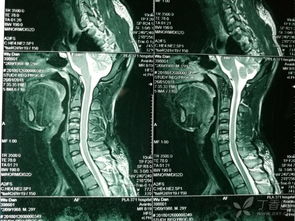

因為頸骨骨折也就是頸部脊椎骨的骨 折,在脊椎骨中央有神經(jīng)通過(guò),這些神經(jīng)像電纜一樣能把大腦的命令傳達到全身,又能把身體的感覺(jué)傳向大腦。如果骨折切斷或壓迫脊椎骨中的神經(jīng),頸以下就會(huì )完 全麻痹,有時(shí)會(huì )使呼吸停止。

3、頸椎骨折常見(jiàn)于跳水誤跳入淺游泳池,或從很高的地方墜落以及交通事故等。

體位護理和體溫監測 保持頭、頸、肩一致性活動(dòng),防止頸椎錯位。翻身時(shí)要一個(gè)人固定頭部,一個(gè)人搬動(dòng)軀干,并注意顱骨牽引,防止滑脫,保持牽引繩與軀干在同一軸線(xiàn)上,床頭抬高15°~30°。顱骨牽引鋼針口處滴75%酒精4~5滴,每日更換敷料一次。由于脊髓損傷,植物神經(jīng)功能紊亂,全身交感神經(jīng)支被切斷,不能適應周?chē)h(huán)境溫度的變化而出現高熱,病人一旦出現高熱,體溫>38.5℃(腋下),即給予物理降溫,必要時(shí)給4℃冰生理鹽水300ml低壓灌腸,采取積極措施降溫。